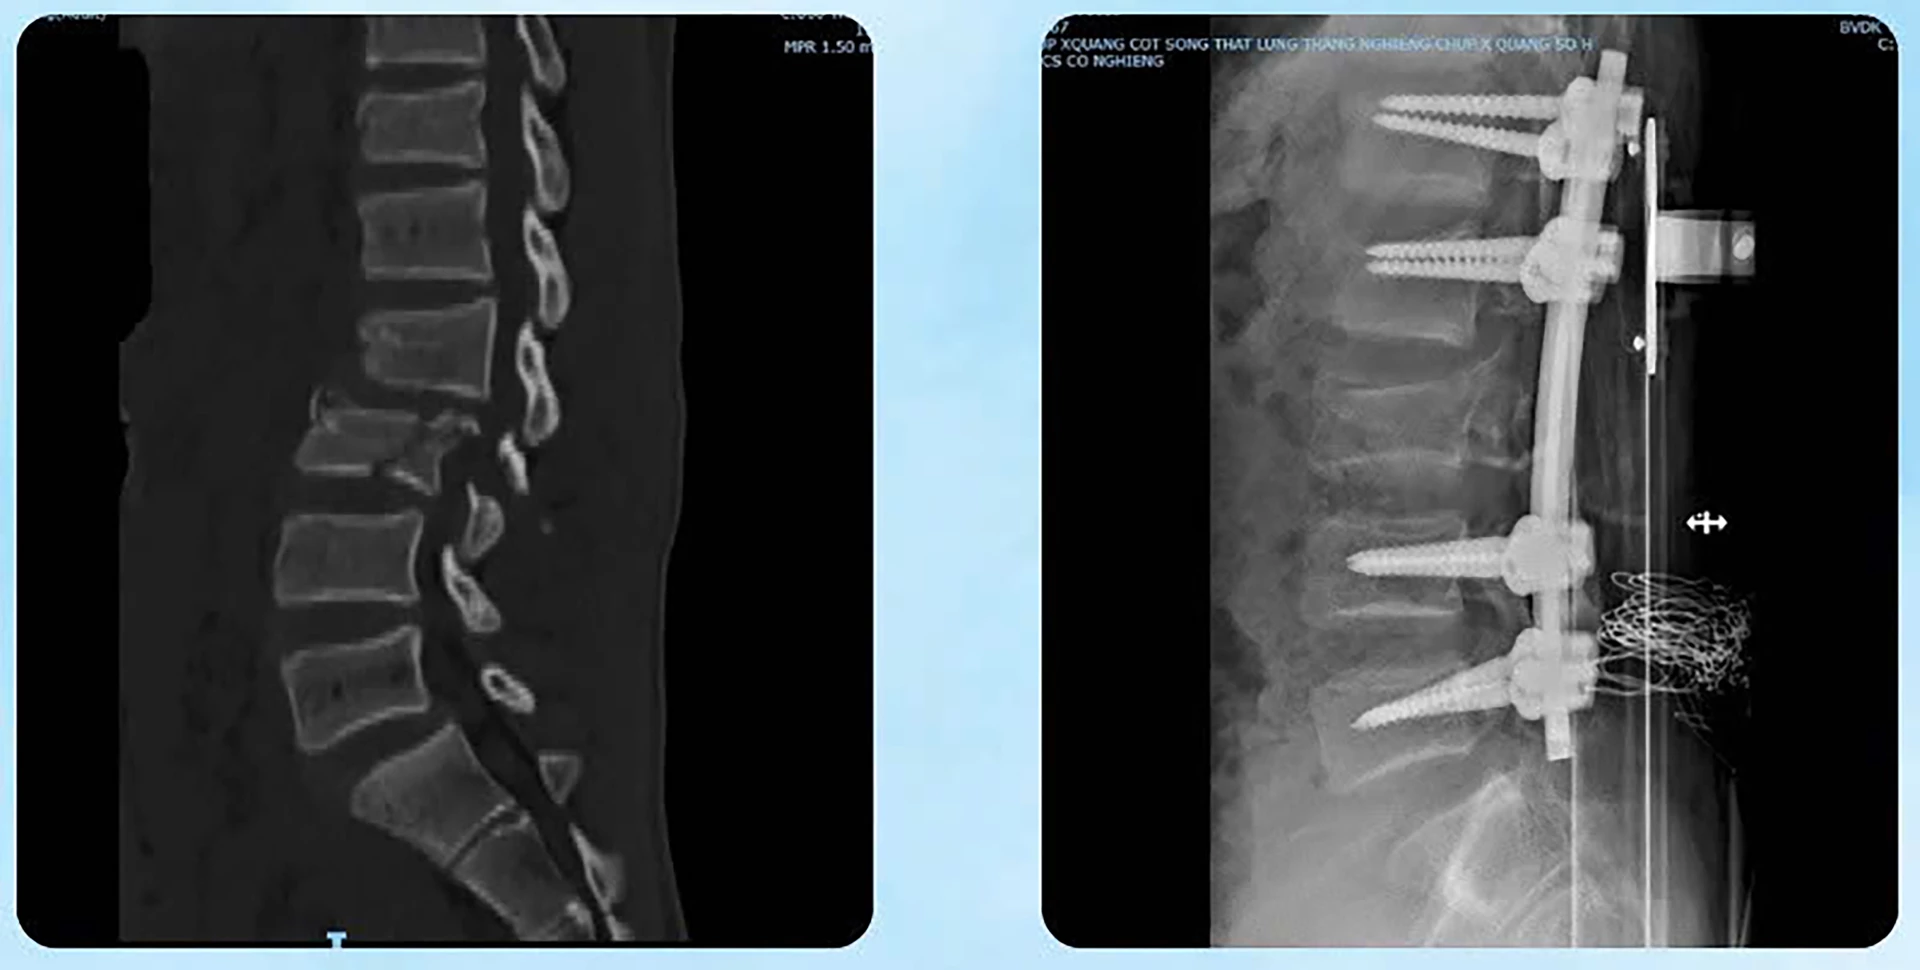

Kết quả chẩn đoán cho thấy, bệnh nhân bị tổn thương nặng ở nhiều cơ quan: Chấn thương ổ bụng, gãy thân xương đùi, tổn thương phần mềm vùng bụng lưng chậu, chấn thương lồng ngực và thận. Đặc biệt, bệnh nhân bị gãy trật cột sống nặng tại đoạn L2–L3, kèm máu tụ ngoài màng tủy, tủy dập và rách màng tủy.

Bệnh nhân đã được phẫu thuật cắt lọc và khâu phục hồi tổn thương đại tràng ngang, đồng thời xử lý dịch máu trong ổ bụng; phẫu thuật vào cột sống lối sau, nắn trật cột sống đoạn L2–L3 và làm vững toàn bộ đoạn cột sống bị tổn thương bằng nẹp vít cuống cung dưới hướng dẫn C-arm; đồng thời cắt bản sống L2–L3, lấy máu tụ ngoài màng tủy giải phóng chèn ép tủy, xử lý vùng tủy dập và vá màng tủy bị tổn thương. Các bác sĩ cũng đã thực hiện phẫu thuật kết hợp xương đùi dưới C-arm bằng đường mổ nhỏ, nắn chỉnh tốt giải phẫu ổ gãy, kết hợp xương bằng nẹp vít khóa cho bệnh nhân H.R.

Phẫu thuật cố định cột sống cho bệnh nhân - Ảnh: HL